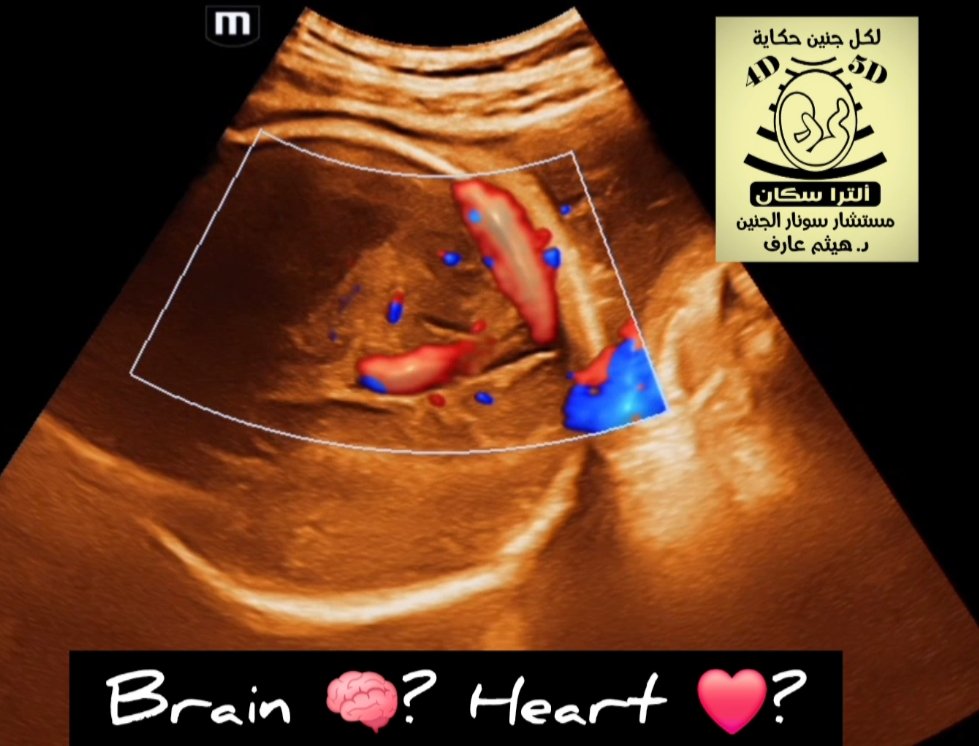

The dilated median prosencephalic vein (MPV appears as an anechoic structure in the midline posteriorly and demonstrates prominent flow on Doppler examination. Shunting may lead to complications such as hydrops fetalis or fetal cardiomegaly.